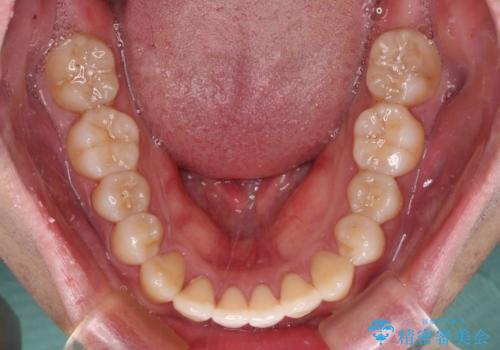

インビザラインで奥歯の咬み合わせと前歯のデコボコを改善

- 前歯のデコボコと奥歯の咬み合わせを気にして来院された患者様です。

前歯のデコボコはインビザラインで十分に対応可能と判断できましたが、咬合力が強いため、臼歯(特に右側)の交叉咬合はインビザライン単体では困難と思われました。

まずはインビザライン単体で矯正治療を開始し、交叉咬合が改善されない場合にはアンカースクリューなどの使用を検討することとしました。

インビザライン単体では右側の交叉咬合を解消することができなかったため、アンカースクリューを併用して咬合を改善させました。